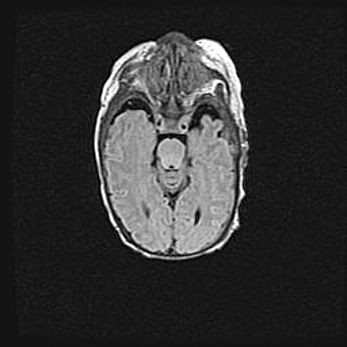

Лейкомаляция с кистозно-глиозной дегенерацией головного мозга.

Возраст: 2 месяца 25 дней

Вес: 6400 г

Окружность головы: 40 см

Срок гестации: 41 неделя

Лейкомаляцию относят к ишемически-гипоксическим повреждениям головного мозга, диагностируемым у новорожденных. При лейкомаляции в головном мозге обнаруживают очаги некроза, возникшие после тяжелой гипоксии и нарушения кровотока. В процессе морфогенеза очаги проходят три стадии: 1) развития некроза, 2) резорбции и 3) формирования глиозного рубца или кисты. Перивентрикулярная лейкомаляция (ПЛ) встречается примерно в 12% случаев среди новорожденных, обычно – у недоношенных детей, причем, частота ее зависит от массы, с которой младенец появился на свет. Наибольшее число малышей страдает лейкомаляцией, если масса при рождении 1500-2500 г.